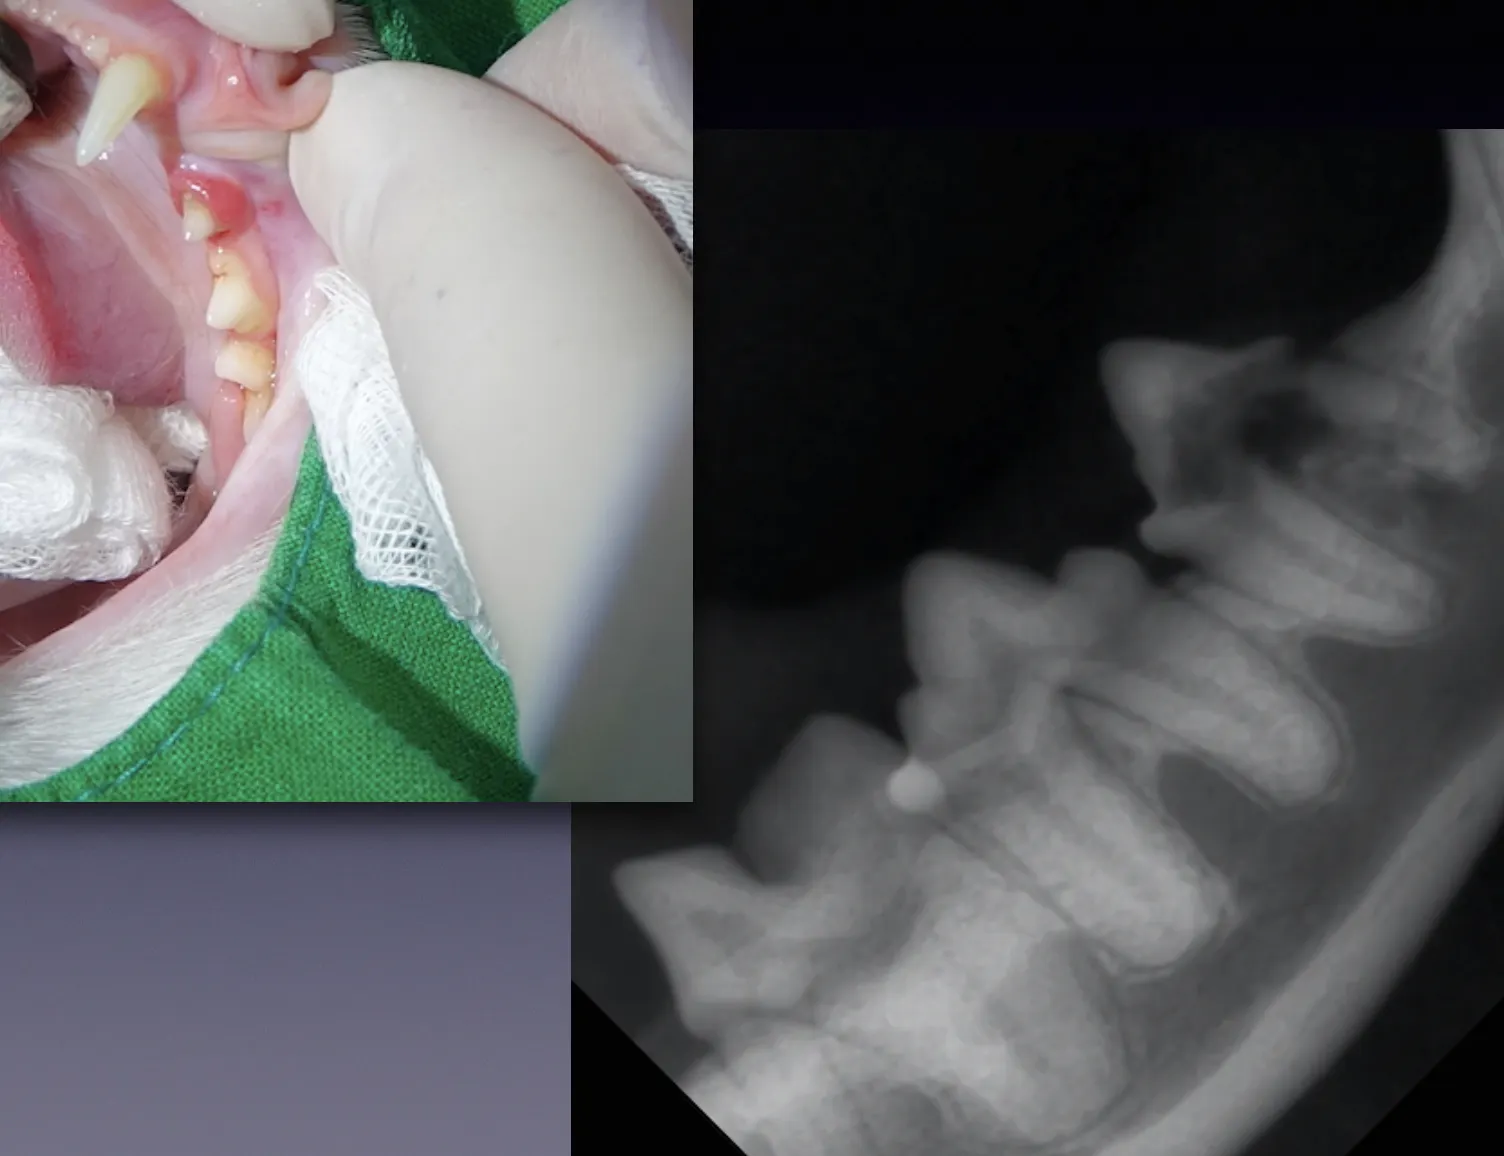

우선 전신 마취 후 치아방사선 촬영 후

치아 뿌리의 상태를 확인하고

치아흡수성 병변이 관찰되는 경우

발치를 진행합니다.